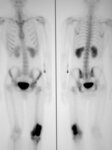

Cintilografia óssea; alta captação de radionuclídeo no local do tumor

Do acervo do Dr. Michael J. Klein e da Dra. Luminita Rezeanu